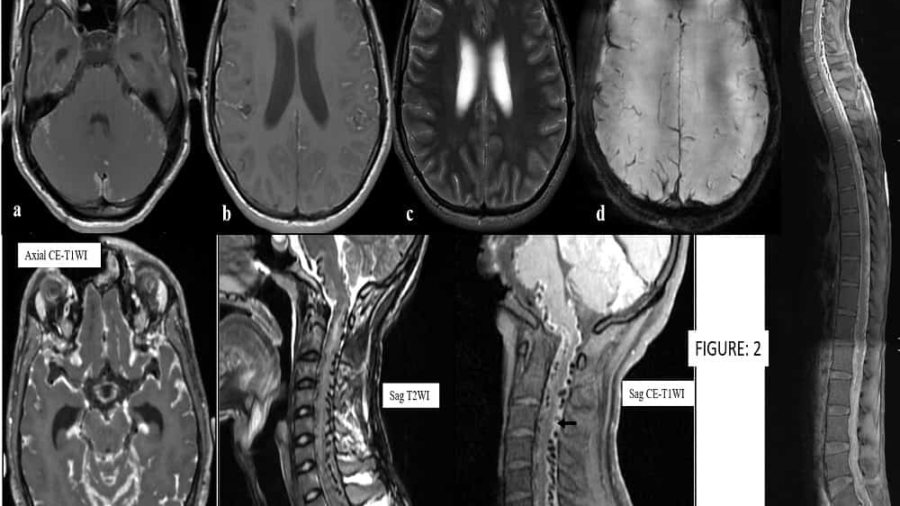

A 22-year-old male presented with complain of headache, vomiting for 4 to 6 weeks. Associated with weakness of all limbs and loss of bladder/bowel control for 10 days.